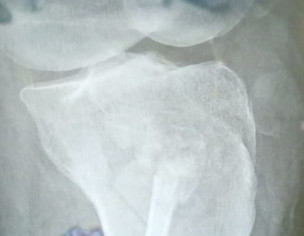

I had an accident on Thursday in which lateral condyle fracture occured.I want to ask it is need for surgery or plaster??

Attach Photo here: